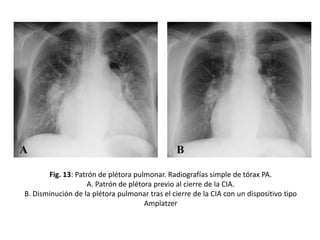

Patrón de plétora pulmonar

• Aumento del flujo en la circulación pulmonar

– Dilatación de los vasos pulmonares centrales y

periféricos de manera bilateral y simétrica

– Acompañada de cardiomegalia a expensas del

corazón derecho.

Fig. 13: Patrón de plétora pulmonar. Radiografías simple de tórax PA.

A. Patrón de plétora previo al cierre de la CIA.

B. Disminución de la plétora pulmonar tras el cierre de la CIA con un dispositivo tipo

Amplatzer